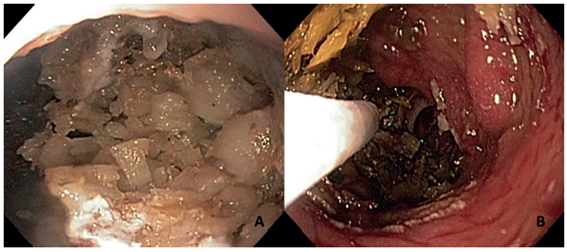

Durante la endoscopia, se encontró un bezoar de coco que obstruía parcialmente la anastomosis gastro-yeyuno, el cual se trituró y los fragmentos fueron removidos endoscópicamente (figura 1). Después de este procedimiento, toleró la ingestión de líquidos y, dos días después, se dio de alta con su dieta normal.

Caso clínico: Se presenta el caso de una mujer de 52 años de edad con antecedentes de diabetes mellitus y obesidad, que fue tratada con una miniderivación gástrica por laparoscopia. Nueve meses después del procedimiento, presentó dolor en el epigastrio, intolerancia a los alimentos y vómito, por lo cual se dio tratamiento sintomático sin obtener mejoría. Se practicó una endoscopia de vías digestivas altas, cuyo hallazgo fue un bezoar de coco que obstruía parcialmente la anastomosis. El bezoar se trituró y se extrajo por endoscopia.

Presentation of case: A fifty-two years old female with type II diabetes mellitus and obesity was treated by laparoscopic mini-gastric bypass surgery. Nine months after her surgery she experienced epigastric pain, intolerance to food and vomiting with non-successful symptomatic treatment. One month later, the patient underwent an upper GI endoscopy which reported a coconut bezoar partially obstructing the anastomosis. Bezoar was broken into pieces and removed endoscopically. Two days after, patient returned to normal diet.